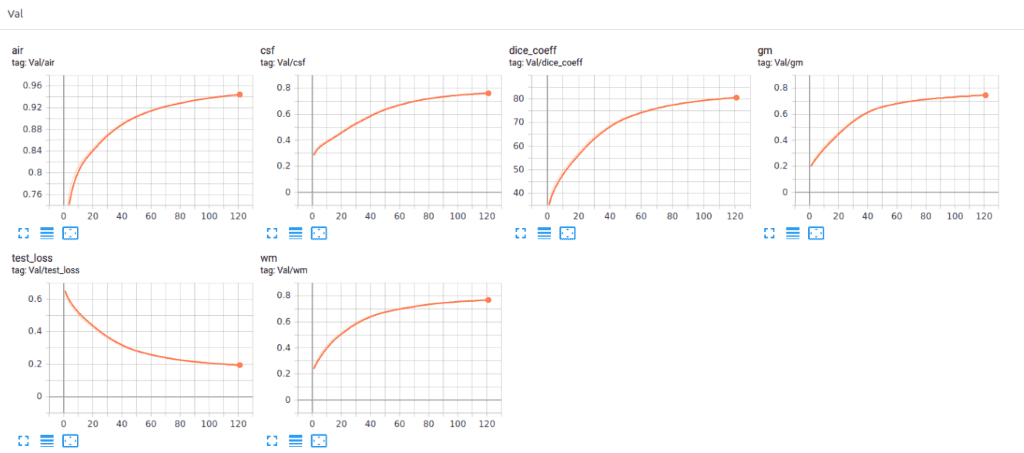

最近我们用 Pytorch 添加了 Tensorboard 可视化。这个惊人的功能可以让您保持清醒,并让您跟踪模型的训练过程。下面你可以看到一个保持训练统计数据的例子,骰子系数。和损失以及每类分数以了解模型行为。

下面你可以看到模型的训练和验证骰子损失曲线。监控您的模型性能并调整参数以获得如此平滑的训练曲线非常重要。很容易理解这个模型的效率。

该模型在子卷的验证集中达到了大约 93% 的骰子系数分数。最后但同样重要的是,让我们看看验证集中 3D-Unet 的一些可视化预测。尽管预测是 3D 体积,但我们在这里只展示一个代表性切片。通过获取 MRI 的多个子体积,可以将它们组合起来形成完整的 3D MRI 分割。请注意,我们使用子卷采样的事实是数据增强。

最近我们还使用 Pytorch 添加了Tensorboard可视化。这个惊人的功能可以让你保持清醒,让你跟踪模型的训练过程。您可以在下面看到一个保留训练统计数据、骰子系数和损失以及每类分数以了解模型行为的示例。

很明显,不同的组织具有不同的精度,即使从训练开始也是如此。例如,查看验证集中从高值开始的空气体素,因为它是不平衡数据集的最主要类别。另一方面,灰质从最低值开始,因为它最难区分且训练实例较少。